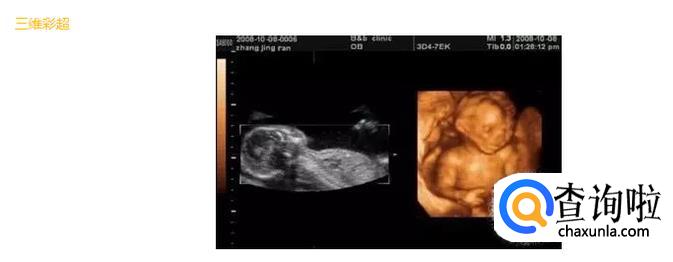

- 04

四维彩超是采用三维超声图像加上时间维度参数,可以更直观更清晰地呈现胎儿在宫内的动态图像,多方位、多角度地观察胎宝宝的生长发育情况。